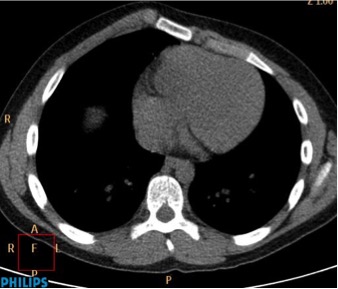

CASO: cáncer de mama. Control anual.

Hallazgos:

- Se observa un aumento de densidad con agrupación broncovascular que produce un borramiento del borde cardicaco derecho; hallazogos compatibles con atelectasia en el lóbulo medio. Véase el TC a continuación: